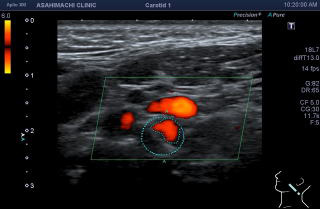

円で囲まれた部分が血管で、赤い部分にしか血液が流れていません。その他の部分はつまっています。脳梗塞のもとになります。このまま放置すると非常に危険です。

円で囲まれた部分が血管で、赤い部分にしか血液が流れていません。その他の部分はプラークで狭くなっています。脳梗塞のもとになります。このまま放置すると非常に危険です。